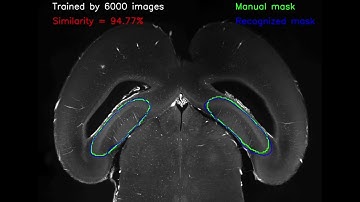

Implementation on Brain Hippocampus Segmentation Using Improved UNET | Python|